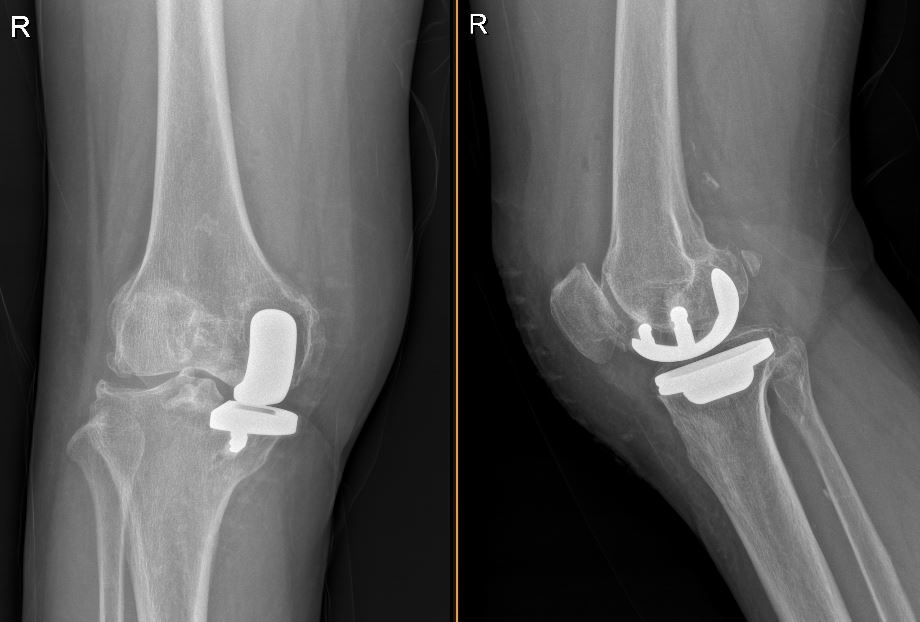

转机出现在她遇到上海市同仁医院骨科程千主任后。华阿姨是通过隔壁邻居介绍前来就诊的,经过细致检查,程主任发现了一个重要细节:华阿姨的膝关节磨损主要局限在内侧间室,这种情况非常适合进行单髁置换手术——这是一种比全膝关节置换更微创的保膝治疗方法。

“单髁置换只需要更换受损的部分关节,”程千主任耐心解释道,“手术创伤更小、保留的骨质更多、术后恢复更快,特别适合像华阿姨这样病变局限的患者。”

术后四个月复查时,华阿姨欣喜地展示手术效果:膝关节疼痛明显缓解,功能恢复良好,而最让她担心的手术疤痕也非常轻微,与之前的手术疤痕形成鲜明对比。

膝关节骨关节炎是常见老年疾病,但治疗方案需要因人而异。单髁置换术作为保膝疗法的重要手段,适用于病变局限于单一间室的患者,具有创伤小、出血少、恢复快、保留本体感觉好的优点。同时术后康复锻炼对关节功能恢复至关重要,患者应在专业指导下循序渐进地进行康复训练。